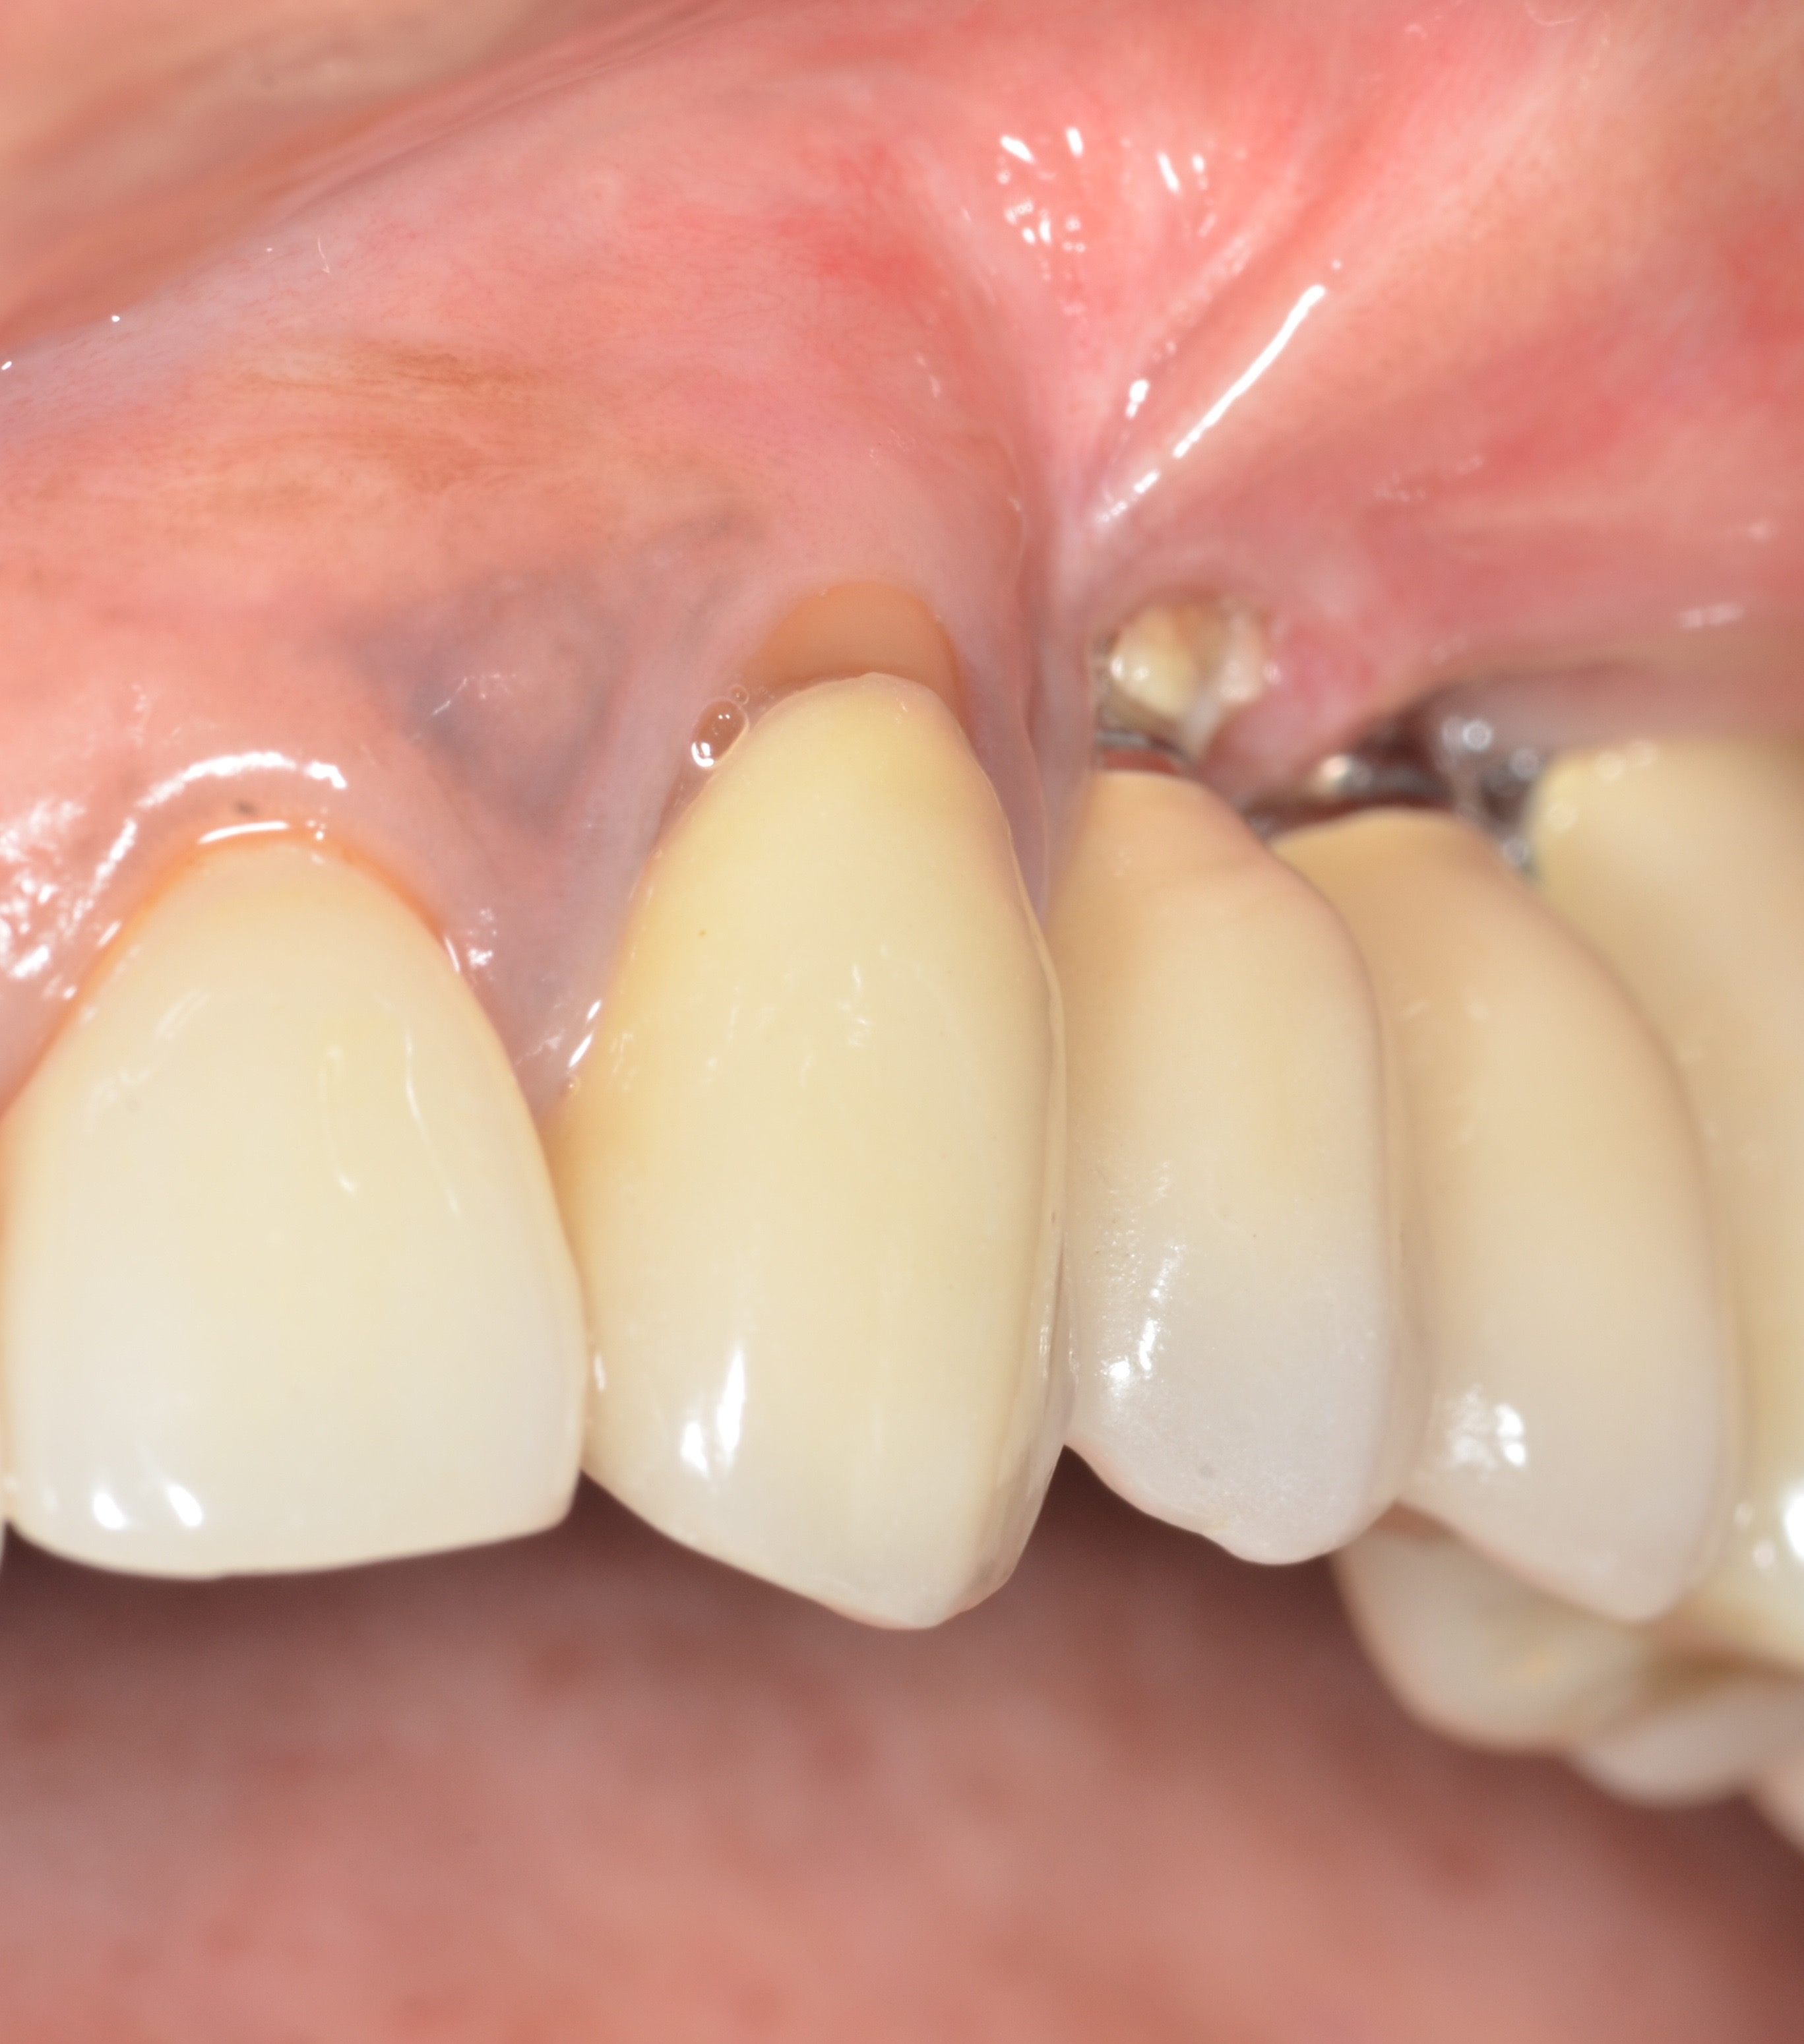

Whether or not to probe around dental implants has been a topic of debate in the dental community for years. Recent consensus supports periodic probing around dental implants so that changes in probing, such as the presence of bleeding on probing, suppuration, and probing depth, can be identified over time.5 If bleeding on probing is present, then the cause(s) of this bleeding should be identified and a proactive treatment approach taken before bone loss begins to occur around the implant. Bleeding may result from poor oral hygiene or a lack of adequate keratinized tissue around the implant (Figure 2). And insufficient keratinized tissue in the presence of poor oral hygiene may lead to an even greater level of peri-implantitis.6 This can result in increases in gingival bleeding, plaque index, pocket depth, and bleeding on probing. Therefore, the presence of adequate thickness and keratinization of soft tissue around dental implants is a necessity.

(2.) Lack of keratinized attached tissue on the buccal aspect of teeth Nos. 11 through 13, resulting in food impaction and detachment from the implant site.

Figure 2